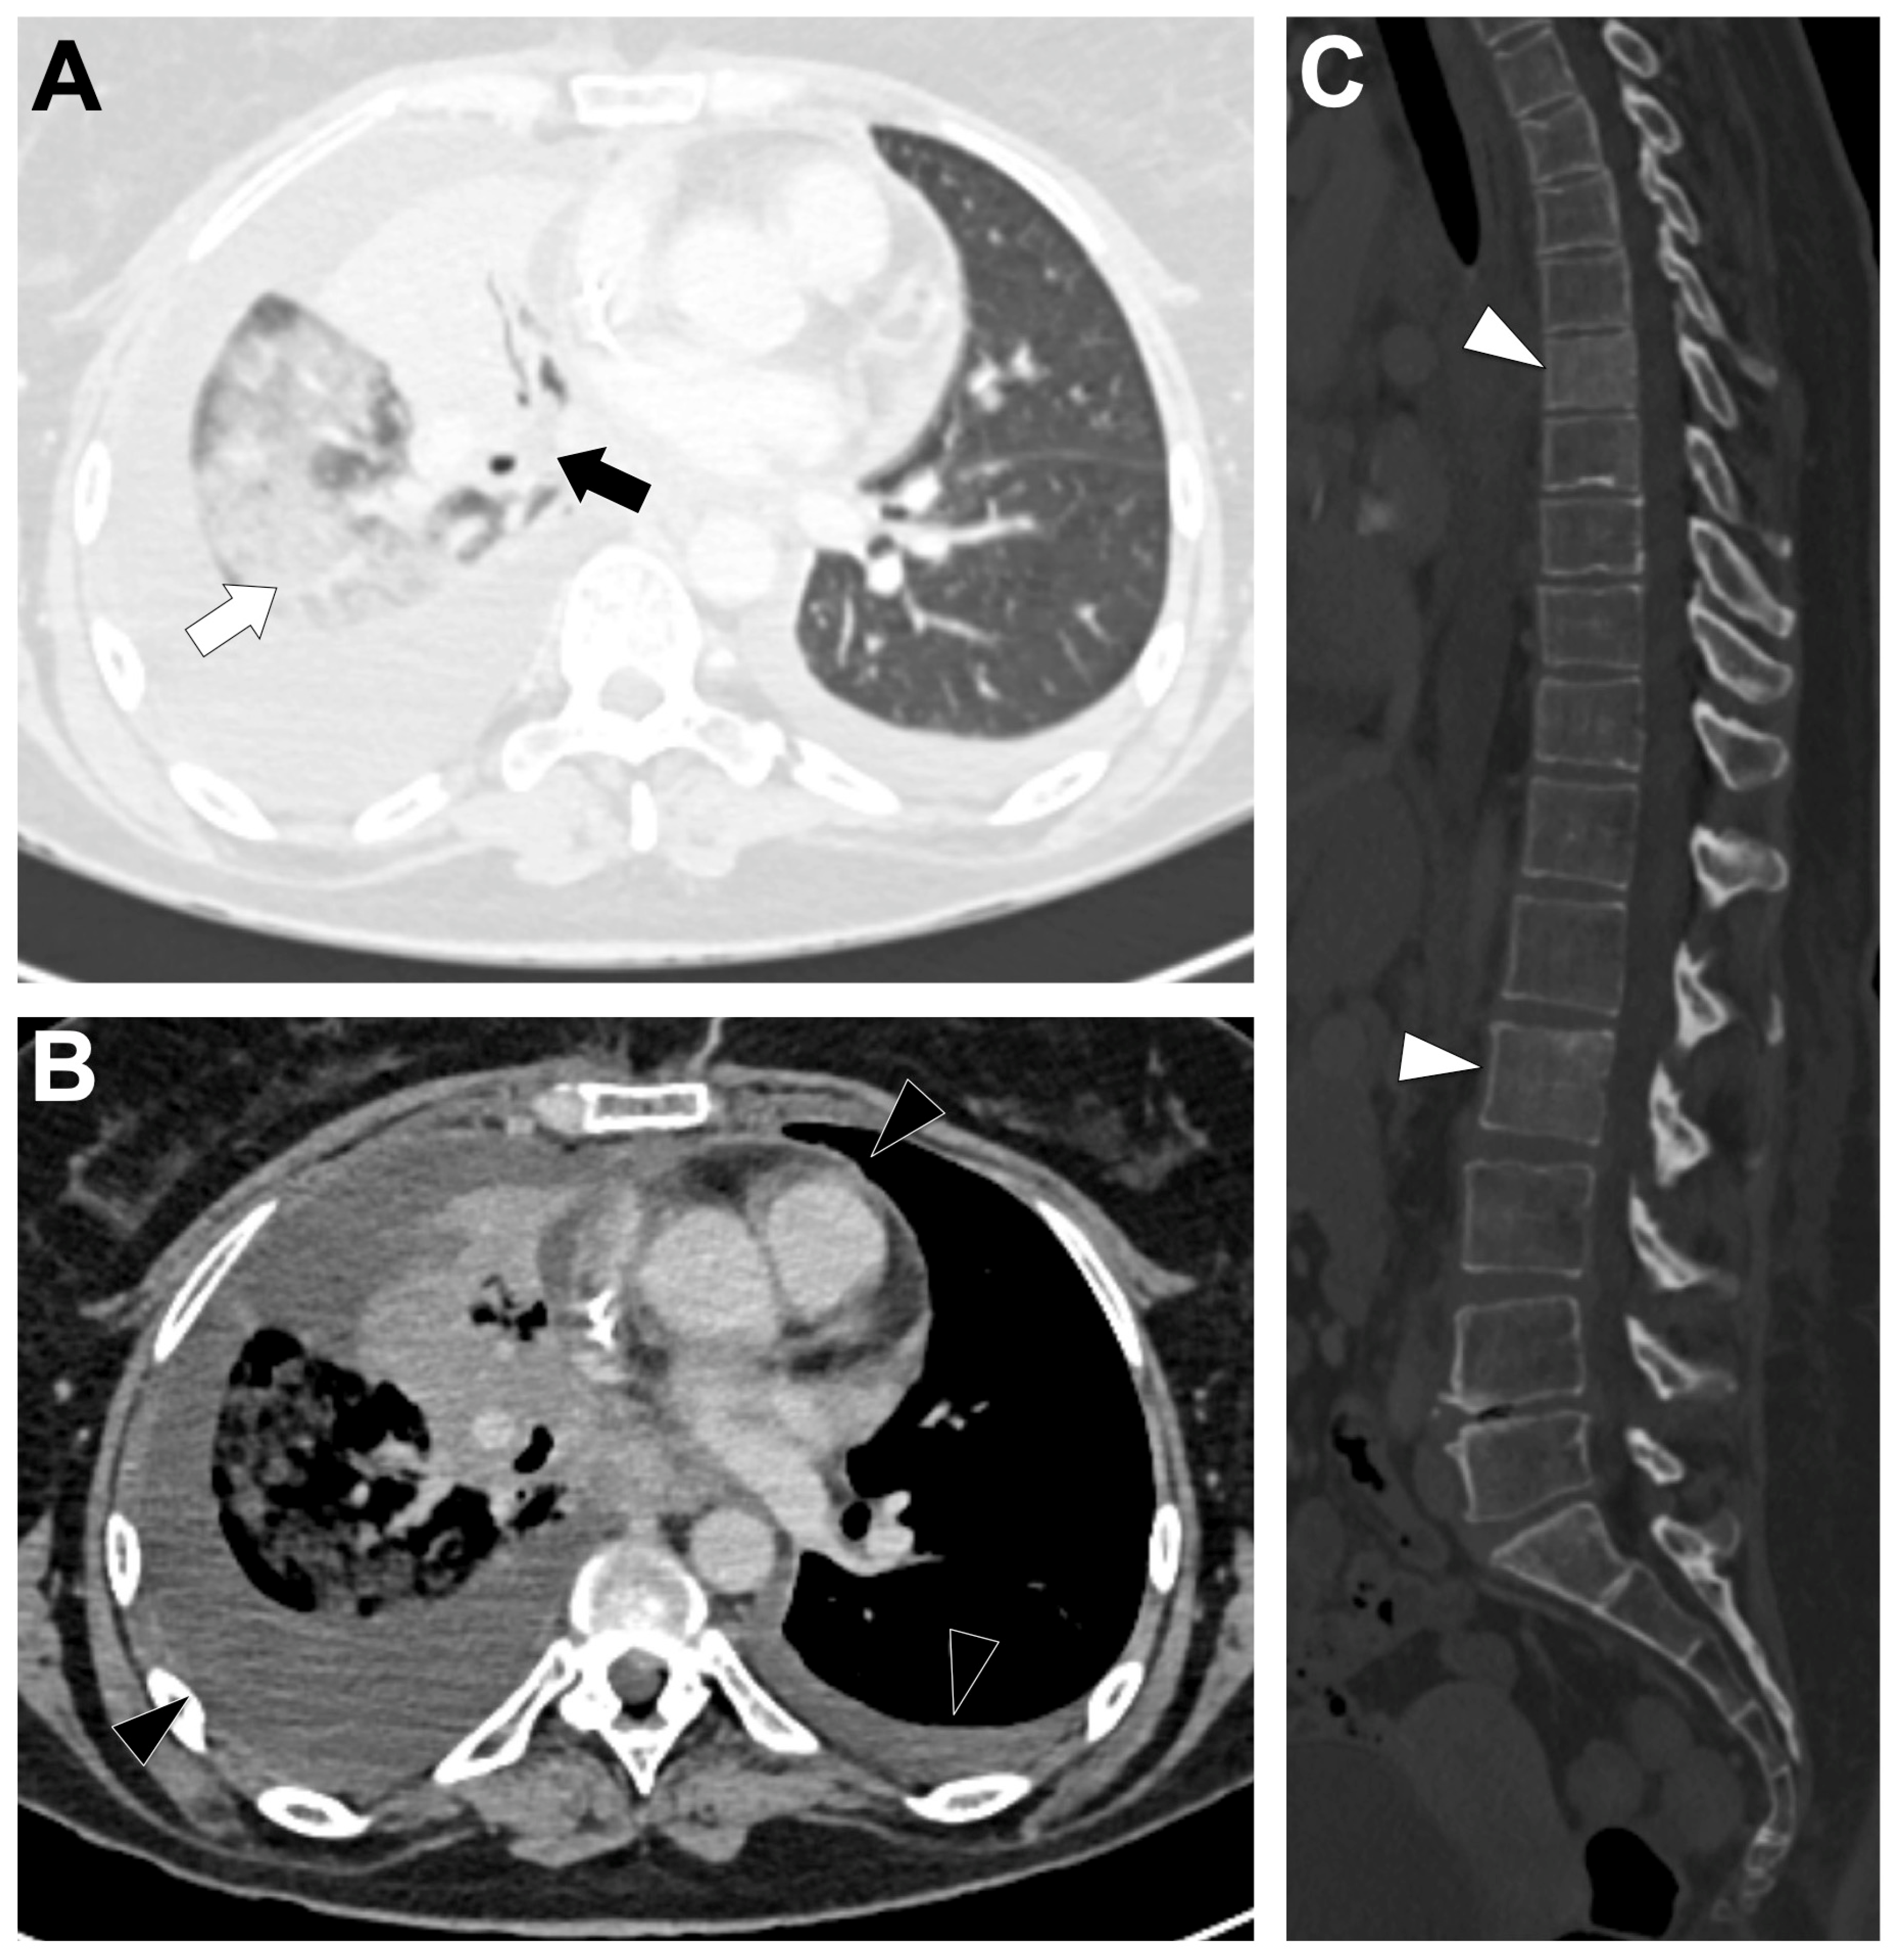

3.2. ALK-Altered NSCLCs

3.2.2. Radiological Characteristics of the Primary Lung Lesion in ALK-Altered LUAD

3.2.4. Metastatic Pattern in ALK-Altered LUAD